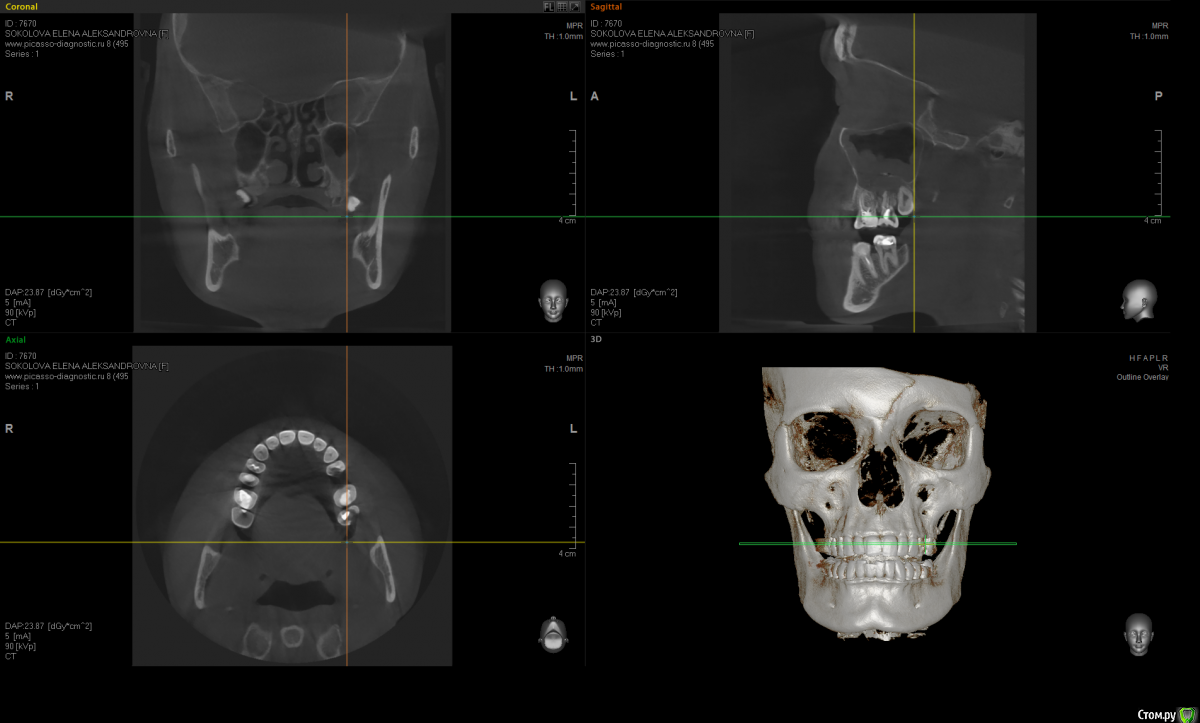

Kostoprav Опубликовано 20 июня, 2015 Поделиться Опубликовано 20 июня, 2015 по данным кт сканам определяеться одонтогенная радикулярная киста в\ч в обл 6,7,8 зубов проросшая в гайморову пазуху + инородное тело (пломбировочный материал ) По моему это работа наша , а не лориков , только санация пазухи не решит проблему Ссылка на комментарий